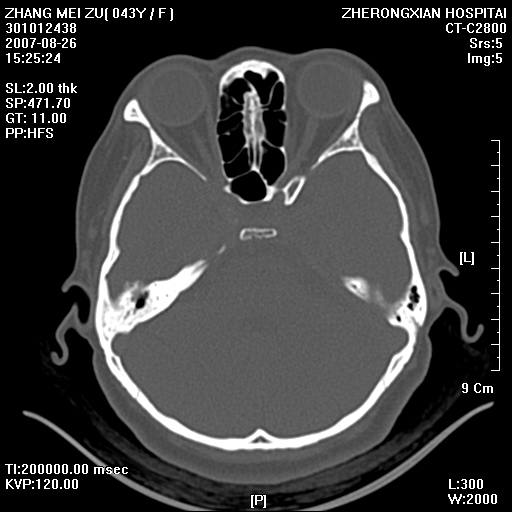

标题: CT9512:F43Y,是肉芽肿还是胆脂瘤?诊断报告该如何出? [打印本页]

标题: CT9512:F43Y,是肉芽肿还是胆脂瘤?诊断报告该如何出?

右耳硬化性乳突炎并胆脂瘤形成

右耳硬化性乳突炎并鼓窦入口胆脂瘤形成,左侧乳突炎

右侧中耳乳突炎,伴鼓窦入口胆脂瘤形成.

从发病部位及骨质破坏应该考虑是获得性胆脂瘤

典型胆脂瘤,从上鼓室,乳突窦入口到乳突窦有明显光滑的骨质破坏和软组织结节均为胆脂瘤特点.而肉芽肿对骨质的破坏是轻微的.值得关注的是乳突后壁被破坏只剩薄薄的一层,如果再不尽快治疗,胆脂瘤如果突破其后壁即可能形成耳源性脑脓肿了.